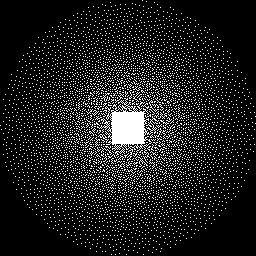

The IAGAN framework was employed to reconstruct images from undersampled ESC k-space data from a slice in a volume in the validation dataset. A volume obtained with the coronal proton density without fat suppression (CORPD) data-acquisition protocol was considered in our reconstruction experiments. The ground truth for comparing reconstructions was obtained by performing the inverse discrete Fourier transform (IDFT) of the fully sampled ESC k-space data. Variable-density Poisson-disc sampling [16] with an acceleration factor of R=8𝑅8R=8 was used to undersample the full raw k-space data (Fig. 2). The sampling pattern was generated using the Berkeley Advanced Reconstruction Tolbox (BART) [17]. Zero-filled (ZF) reconstruction refers to the IDFT of the k-space zero-filled after subsampling and contains severe aliasing artifacts. As a reference, we consider a penalized least squares solution with TV penalty (PLS-TV) as in Eq.(2), obtained by using the BART toolbox. The hyperparameter λ𝜆\lambda was chosen by peforming a grid search and selecting the value that resulted in the lowest mean square error (MSE) of the reconstructed image with respect to the ground truth. Images were reconstructed with the CSGM, IAGAN and IAGAN-TV methods using Tensorflow [15]. The Adam optimizer [18] was used to perform stochastic gradient descent for solving Eq.(4), Eq.(5) and Eq.(6) respectively.

Refer to caption

Figure 2: Variable-density Poisson-disc sampling pattern in k-space with acceleration factor R=8𝑅8R=8. The central 32×32323232\times 32 region of the k-space is fully sampled.